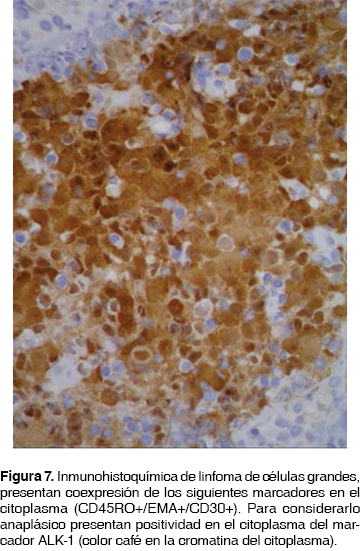

Por los hallazgos mencionados y como parte del protocolo se le realizó PET-CT (figura 3) encontrando una masa en bronquio principal derecho con actividad metabólica de 12 SUV. Se realizó una broncoscopia con los siguientes hallazgos: en la emergencia del bronquio principal derecho a 1.5 cm de la carina principal, había una lesión (figura 4) que abarcaba más del 90% de la luz del bronquio principal derecho. La lesión contaba con bordes bien definidos, despulidos, blanquecinos y fácilmente sangrantes (figura 5). Se tomaron biopsias por pinza, cepillado y lavado bronquial. La citología de lavado y cepillado bronquial fue positiva para células neoplásicas malignas que favorecen a linfoma (figura 6), las biopsias bronquiales reportaron infiltración por linfoma anaplásico de células grandes, ALK-1 positivo (CD45RO+/EMA+/CD30+) (figura 7), la biopsia de médula ósea negativa a infiltración, serología para VIH negativa. Se estableció un esquema de quimioterapia a base de ciclofosfamida, hidroxidoxorrubicina, vincristina y prednisona. La consulta de control a los tres meses del diagnóstico con resultado de PET-CT de control reportó masa en bronquio derecho con actividad metabólica de 3 SUV, no evidenció otras lesiones con actividad metabólica. Se continuó seguimiento por consulta externa.